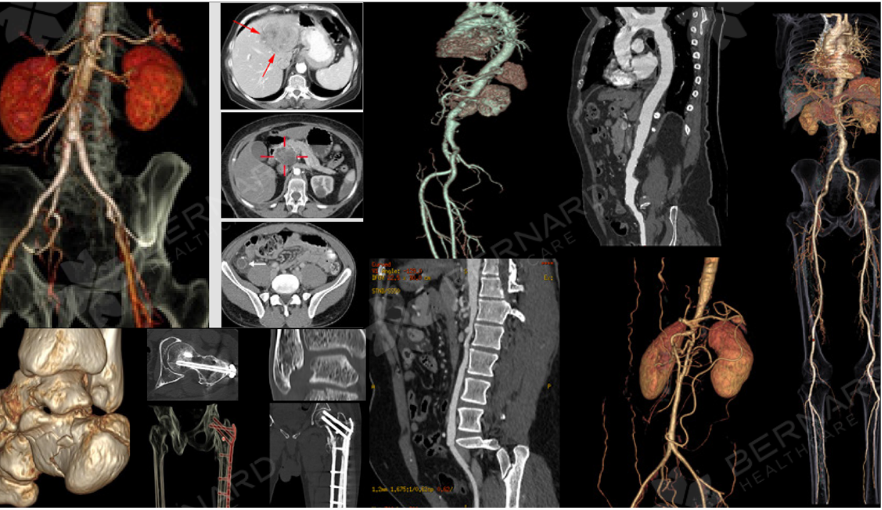

Trên cơ sở đó, bệnh nhân được chỉ định chụp CT Scan cổ - ngực - bụng - chậu nhằm đánh giá toàn diện khả năng di căn và xác định mức độ tiến triển của bệnh.

Kết quả CT Scan ghi nhận có khối choán chỗ khẩu hầu mức amygdale (phải), kích thước 1,9 x 2,1 cm, bờ không đều, bắt quang trung bình, nghi ngờ u ác và hạch lớn khoang cảnh phải (2 x 2,9 cm), bắt quang không đồng nhất, có hoại tử. Những đặc điểm này gợi ý tổn thương đã di căn hạch cổ.

Các cơ quan tim, phổi, gan-thận không ghi nhận bất thường ác tính, chỉ có một số tổn thương xương cũ và thoái hóa cột sống đi kèm.

Kết luận từ chuyên gia chẩn đoán hình ảnh Bernard là tổn thương choán chỗ amidan phải kèm hạch lớn vùng cổ phải, phù hợp phân loại T2N1Mx (giai đoạn III). Điều này cho thấy khối u đã lan đến hệ bạch huyết vùng cổ - tức đã có di căn hạch vùng.